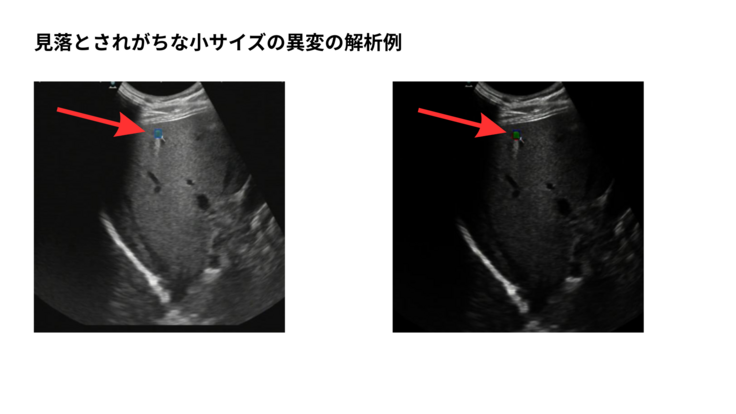

私たちはこれまで、甲状腺や肝臓に現れるがん、血管瘤の異常、肝嚢胞など、

見過ごされやすい病変に数多く出会ってきました。

すでに、以下の高精度なAIモデルが構築済みです

・甲状腺腫瘍の自動検出・良性/悪性分類

・肝臓領域のがん、血管瘤、肝嚢胞の検出